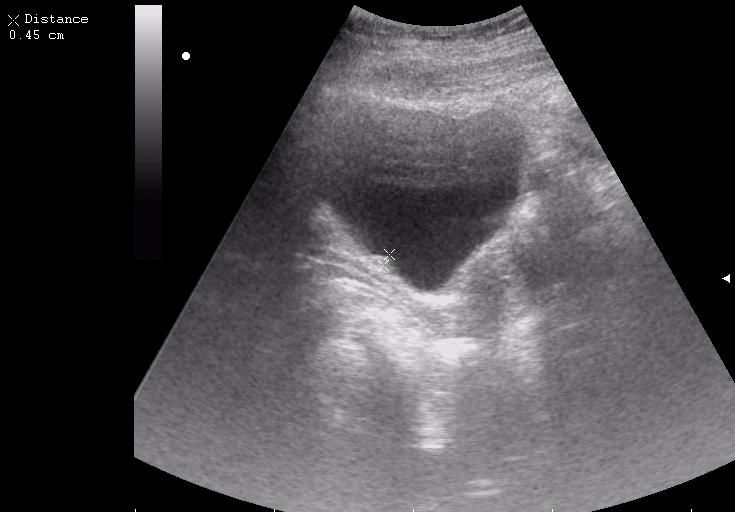

Сравните

Продольное сканирование мочевого пузыря После легкой перкуссии мочевого пузыря